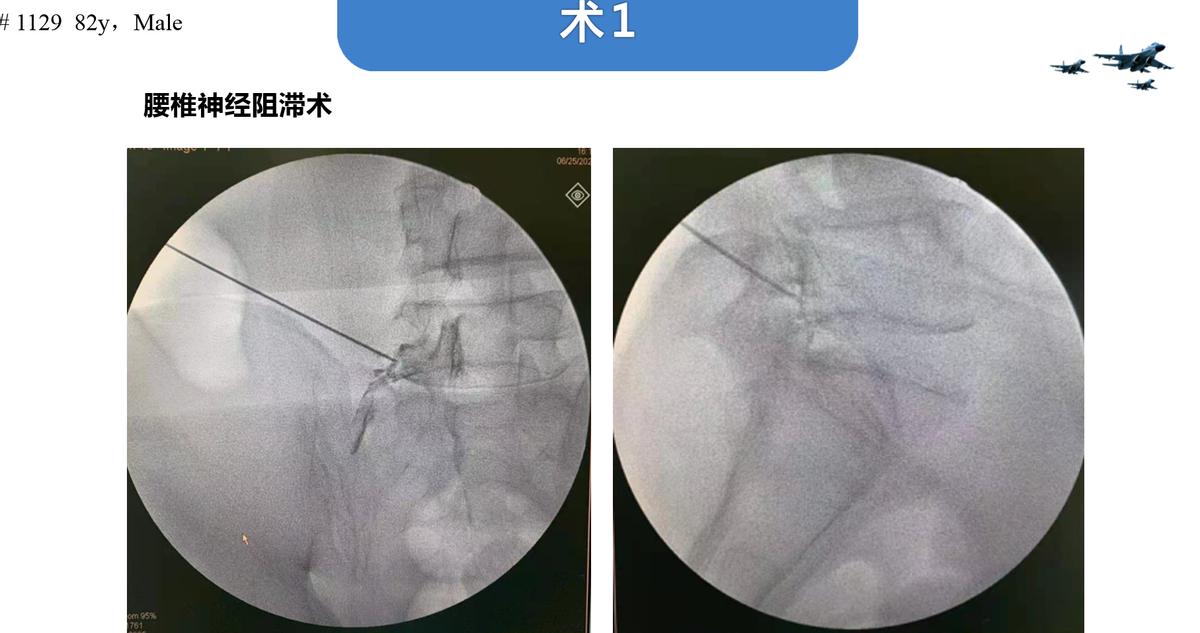

由于患者Cobb角在30°左右,廖博主任团队决定进行“责任节段+X”短节段固定。为了精确责任节段,给患者进行了L5神经根选择性阻滞,原有症状没有诱发和缓解。因此,排除L4/5,将责任节段明确定位到L3/4。最终治疗方案决定为进行 L3/4的TLIF手术,钉道强化,L3椎体强化,术后进行长期的抗骨质疏松治疗。